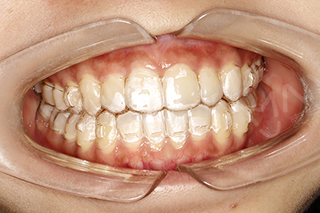

张超主任介绍到:“美国Invisalign隐适美隐形无托槽矫治器由透明医学塑料制造,外表近乎透明,牙套也类似一般用作漂白牙齿的牙套,厚度更少于1mm,戴上后会紧贴牙齿,所以也可以比作牙齿的「隐形眼镜」,拥有随时摘戴、方便清洁、佩戴舒适、不需全天佩戴等众多优点!”